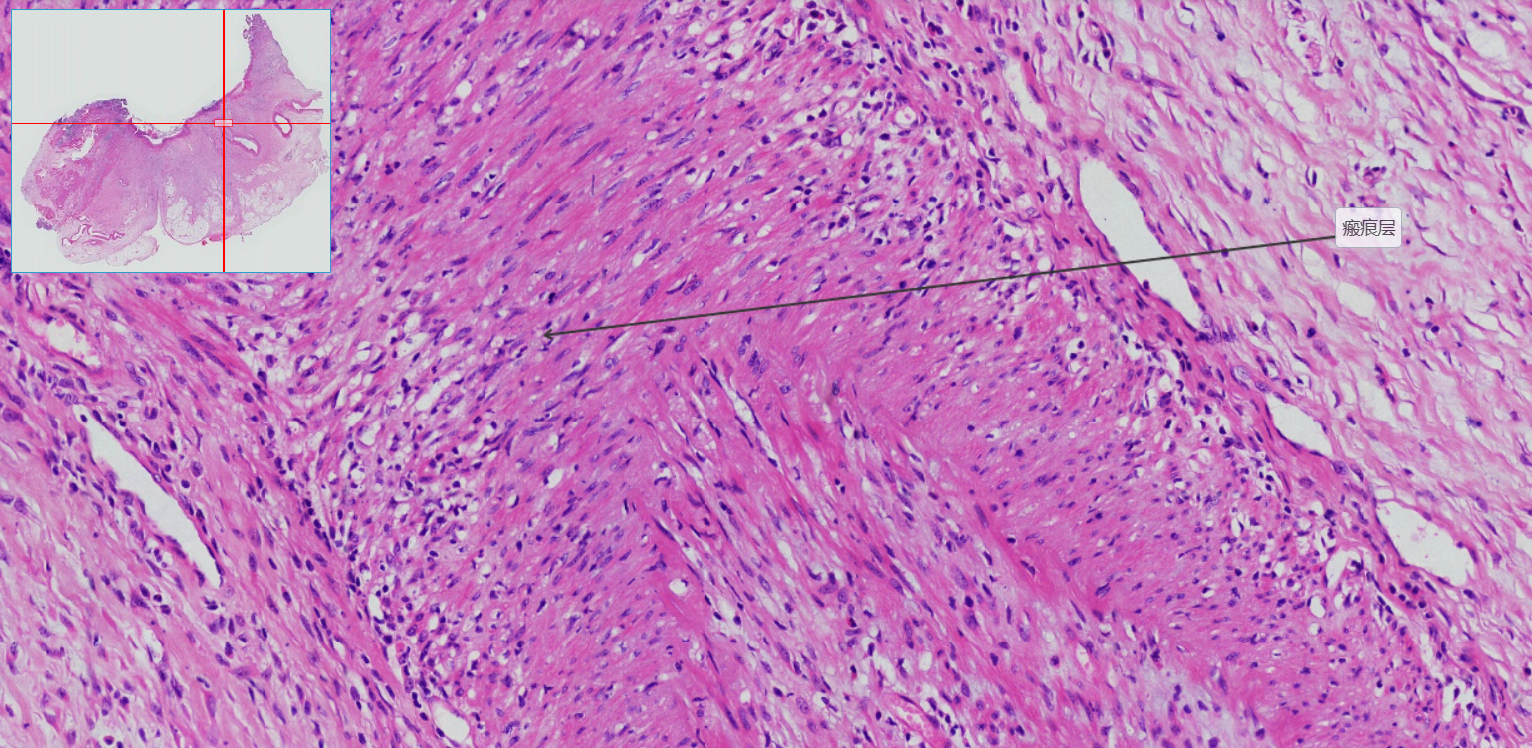

4.瘢痕层

5.小动脉管壁增厚